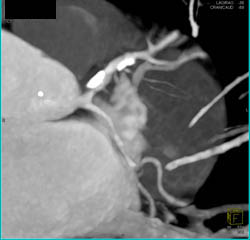

Non-calcified and Calcified Plaque in LAD